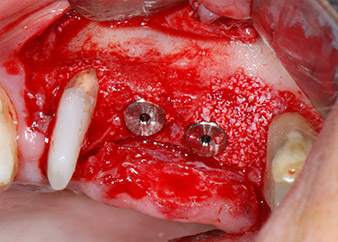

IImplant beds were prepared at sites 25 and 26 with rotary instruments, used in a contra-angle handpiece with a 20 : 1 transmission ratio with an updated powerful implant motor (Implantmed, W&H) (Fig. 8).

The final preparation next to the sinus was again carried out with a piezoelectric instrument (Piezomed, insert S2).

Prior to implant placement, and following verification of an intact Schneiderian membrane (Fig. 9), the internal sinus floor was augmented at both implant sites by means of xenogeneic bone substitute material (Bio-Oss, Geistlich Biomaterials) (Fig. 10).

The implants (Restore, Keystone Dental, diameter 3,75 mm, length 8.0 mm) were placed with the implant motor (Figs. 11 and 12).

Fig. 12: Both implants in place and ready for the cover screws.